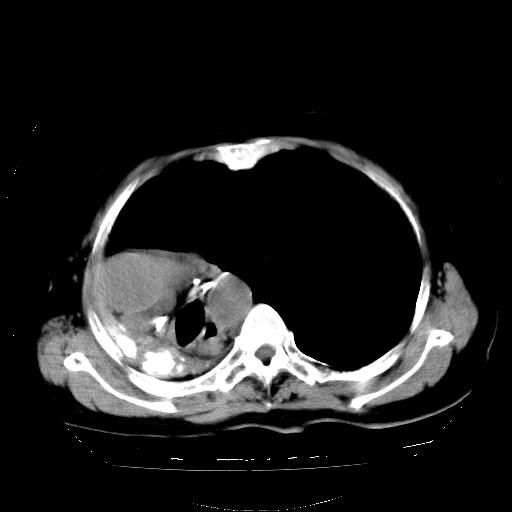

标题: CT23991:女,72岁,咳嗽、憋气一周。 [打印本页]

女,72岁,咳嗽、憋气一周,十年前曾患肺结核及胸膜结核。

1.右侧损毁肺伴胸膜钙化,2.左肺小结节灶,良性可能大,注意复查。3.肝脏左叶囊肿。4.先天性一侧肺不发育待出外(右侧胸廓无明显塌陷)。对比原片应该非常有帮助。